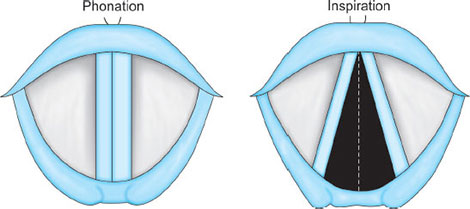

Laryngeal Cavity

Extends from the laryngeal inlet to the lower border of the cricoid cartilage. It consists of the superiorly placed vestibular folds (false cords), and vocal folds (true vocal cords). The space between the true cords is called the rima glottidis, or the glottis. The glottis is divided into two parts—anterior intermembranous section (situated between the two vocal folds) and posterior intercartilaginous part (which passes between the two arytenoid cartilages and the mucosa, stretching between them in the midline posteriorly, forming the posterior commissure of the larynx).

The glottic chink appears oblique during phonation. The aryepiglottic fold on the affected side appears shortened and the one on the normal side is lengthened. The cords may appear wavy. The symptoms include frequent throat clearing and difficulty in raising the vocal pitch. A total bilateral paralysis of vagus nerves affects the recurrent laryngeal nerves and the superior laryngeal nerves. In this condition, the cords assume the abducted, cadaveric position. The vocal cords are relaxed and appear wavy. A similar picture may be seen following the use of muscle relaxants.

Fig. 12A: Position of vocal cords during phonation and inspiration.Source: Hodder Headline PLC, London.

Injury to the recurrent nerve is an obvious hazard of thyroidectomy, especially since the nerve may be displaced from its normal anatomical location by a diseased thyroid gland. Recurrent laryngeal nerve paralysis may occur not only as a result of injury at thyroidectomy but also from involvement of the nerve by a malignant or occasionally benign enlargement of the thyroid gland, by enlarged lymph nodes or by cervical trauma. The recurrent laryngeal nerve carries both abductor and adductor fibers to the vocal cords. The abductor fibers are more vulnerable, and moderate trauma causes a pure abductor paralysis (Selmon's law). Severe trauma causes both abductor and adductor fibers to be affected. Pure adductor paralysis does not occur as a clinical entity. In the case of pure unilateral abductor palsy, both cords meet in the midline on phonation (since adduction is still possible on the affected side). However, only the normal cord abducts during inspiration.13

In the case of complete unilateral palsy of the recurrent laryngeal nerve, both abductors and adductors are affected. On phonation, the unaffected cord crosses the midline to meet its paralyzed counterpart, appearing to lie in front of the affected cord. On inspiration, the unaffected cord moves to full abduction. When abductor fibers are damaged bilaterally (incomplete bilateral damage to the recurrent laryngeal nerve), the adductor fibers draw the cords toward each other and the glottic opening is reduced to a slit, resulting in severe respiratory distress. However, with a complete palsy, each vocal cord lies midway between abduction and adduction and a reasonable glottic opening exists. Thus, bilateral incomplete palsy is more dangerous than the complete variety.